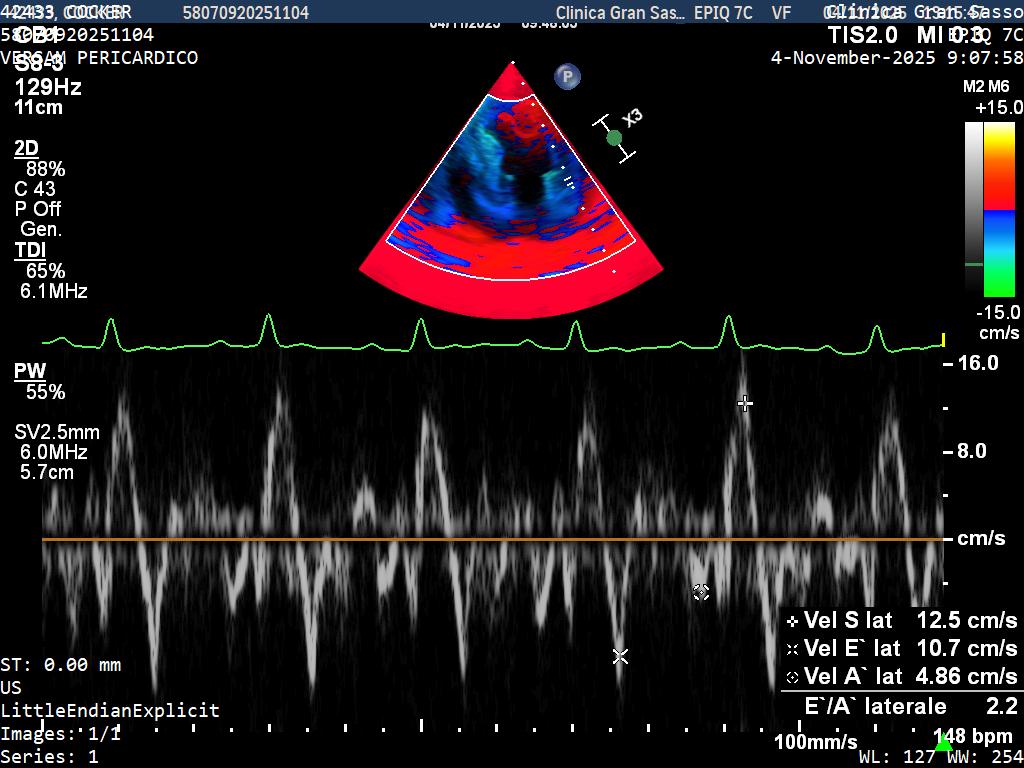

Comprehensive cardiac evaluations are offered including: cardiac examination, echocardiogram (cardiac ultrasound), ECG, 24h Holter monitor, Blood pressure monitor.